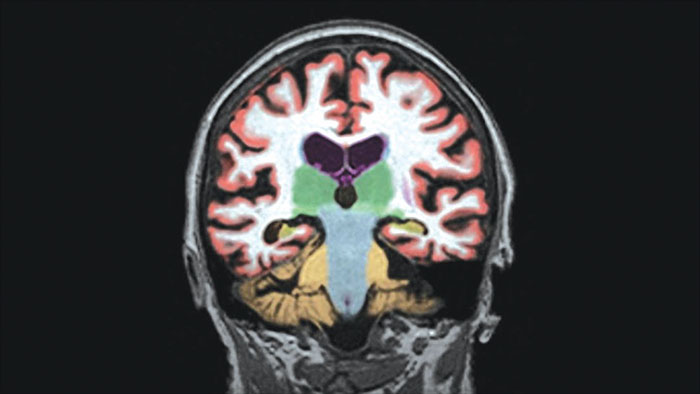

Automated brain image analysis solutions

MR NeuroQuant®* automatically segments and measures volumes of brain structures and compares these volumes to standard norms.